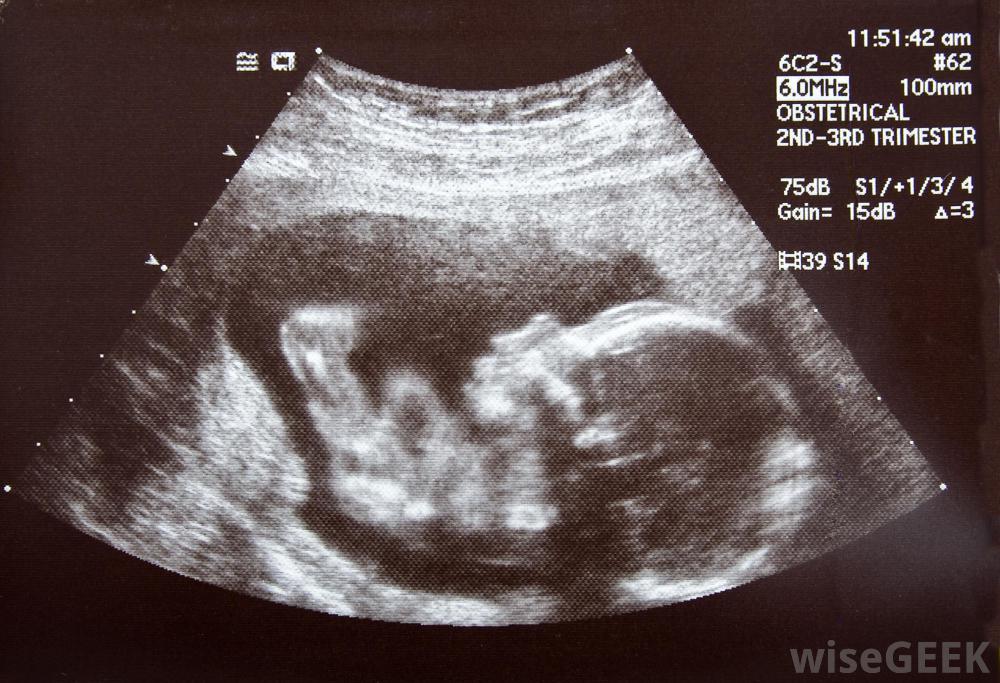

超声波和其他测试有助于确定需要胎儿干预的问题。宫外产时治疗(EXIT)是一种在婴儿准备分娩时进行的胎儿干预。通常是这样当婴儿的呼吸道阻塞,一旦与胎盘分离,就无法正常呼吸时进行。然而,这涉及到剖腹产,与开放式胎儿手术一样,母亲也要接受全身麻醉,然后部分分娩,但直到成功清除呼吸道后,才与脐带分离一旦外科医生确信婴儿可以呼吸,就可以完全分娩。胎儿镜介入术,或者说胎儿胚胎手术,是一种微创的手术,在某些类型的先天性疾病中经常代替开放式胎儿手术。与开放式胎儿手术不同,不用打开腹部或子宫,尽管母亲在手术过程中通常是睡着的,但这种类型的胎儿干预是在子宫内进行的,包括将管子穿过母亲的腹壁和子宫壁。通过这些管子插入仪器和望远镜来进行手术。进行胎儿镜干预的外科医生由望远镜和超声波提供的实时图像引导。对胎儿进行干预的最小侵入性程序称为胎儿图像引导手术(FIGS-IT)。它是利用超声波对胎儿进行实时成像的。这种手术只需将针穿过母亲的腹部,子宫壁区域或局部麻醉通常是这类干预所需的全部,但在极少数情况下可能需要全身麻醉。可能涉及胎儿图像引导干预的预防性治疗可能包括采血或在膀胱内放置导管,但一般来说,在需要手术的情况下,它不用于更复杂的干预。